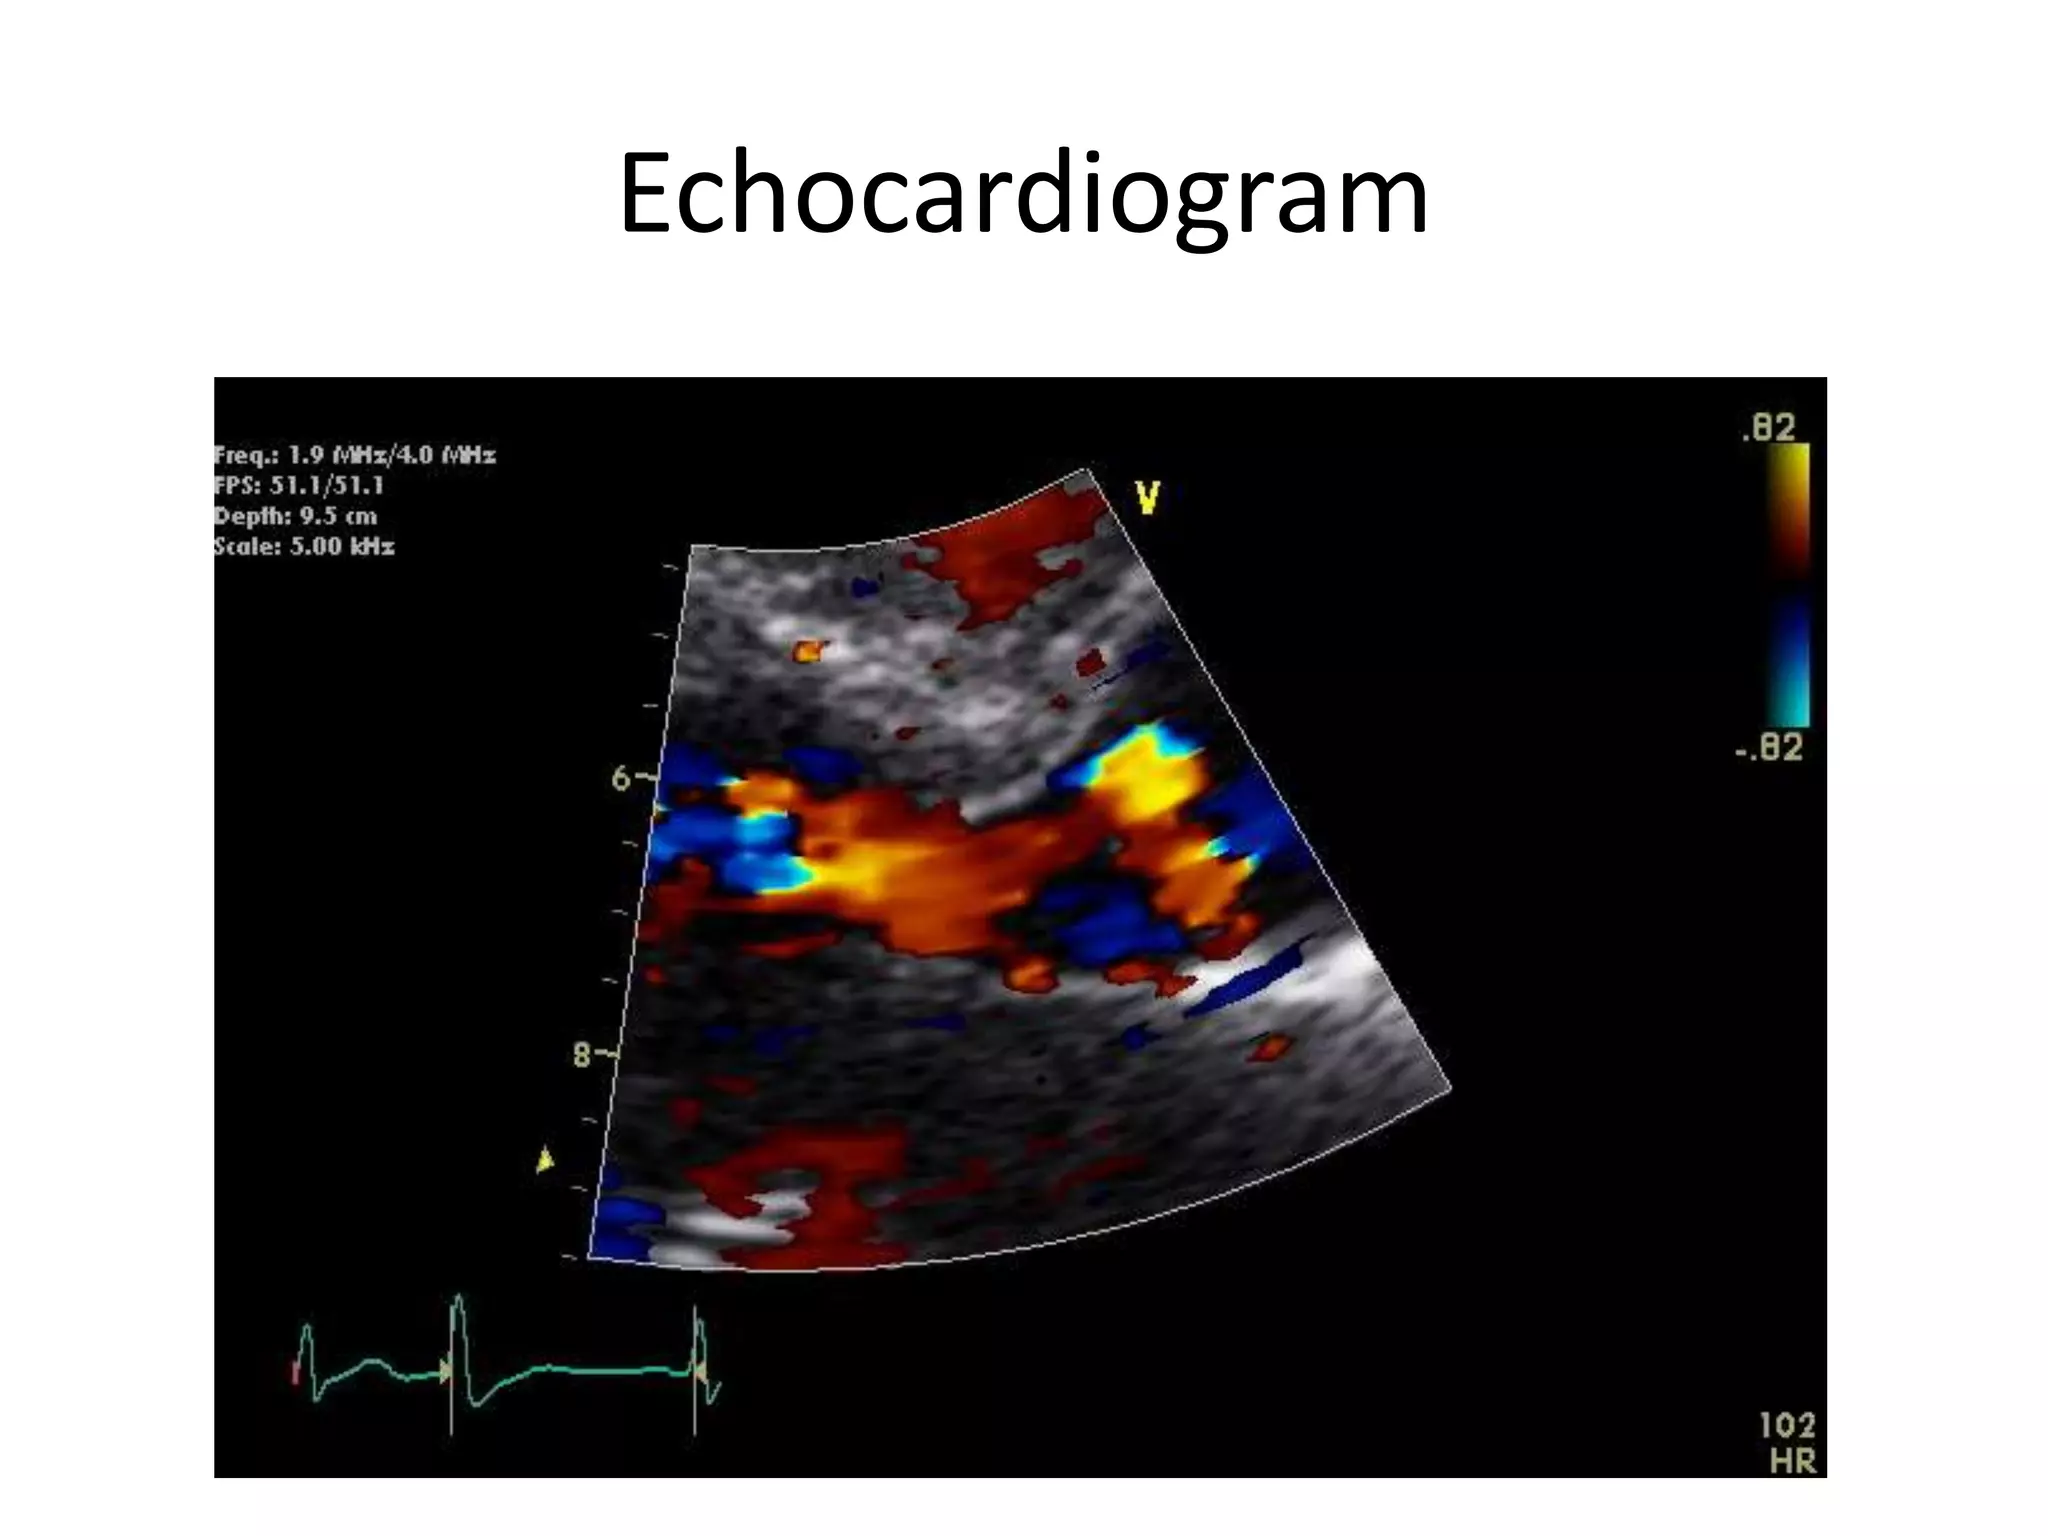

Investigations

• Transthoracic echocardiogram performed

Echocardiogram

Investigations • Two furthersets of blood cultures were sent • Transthoracic echocardiogram performed